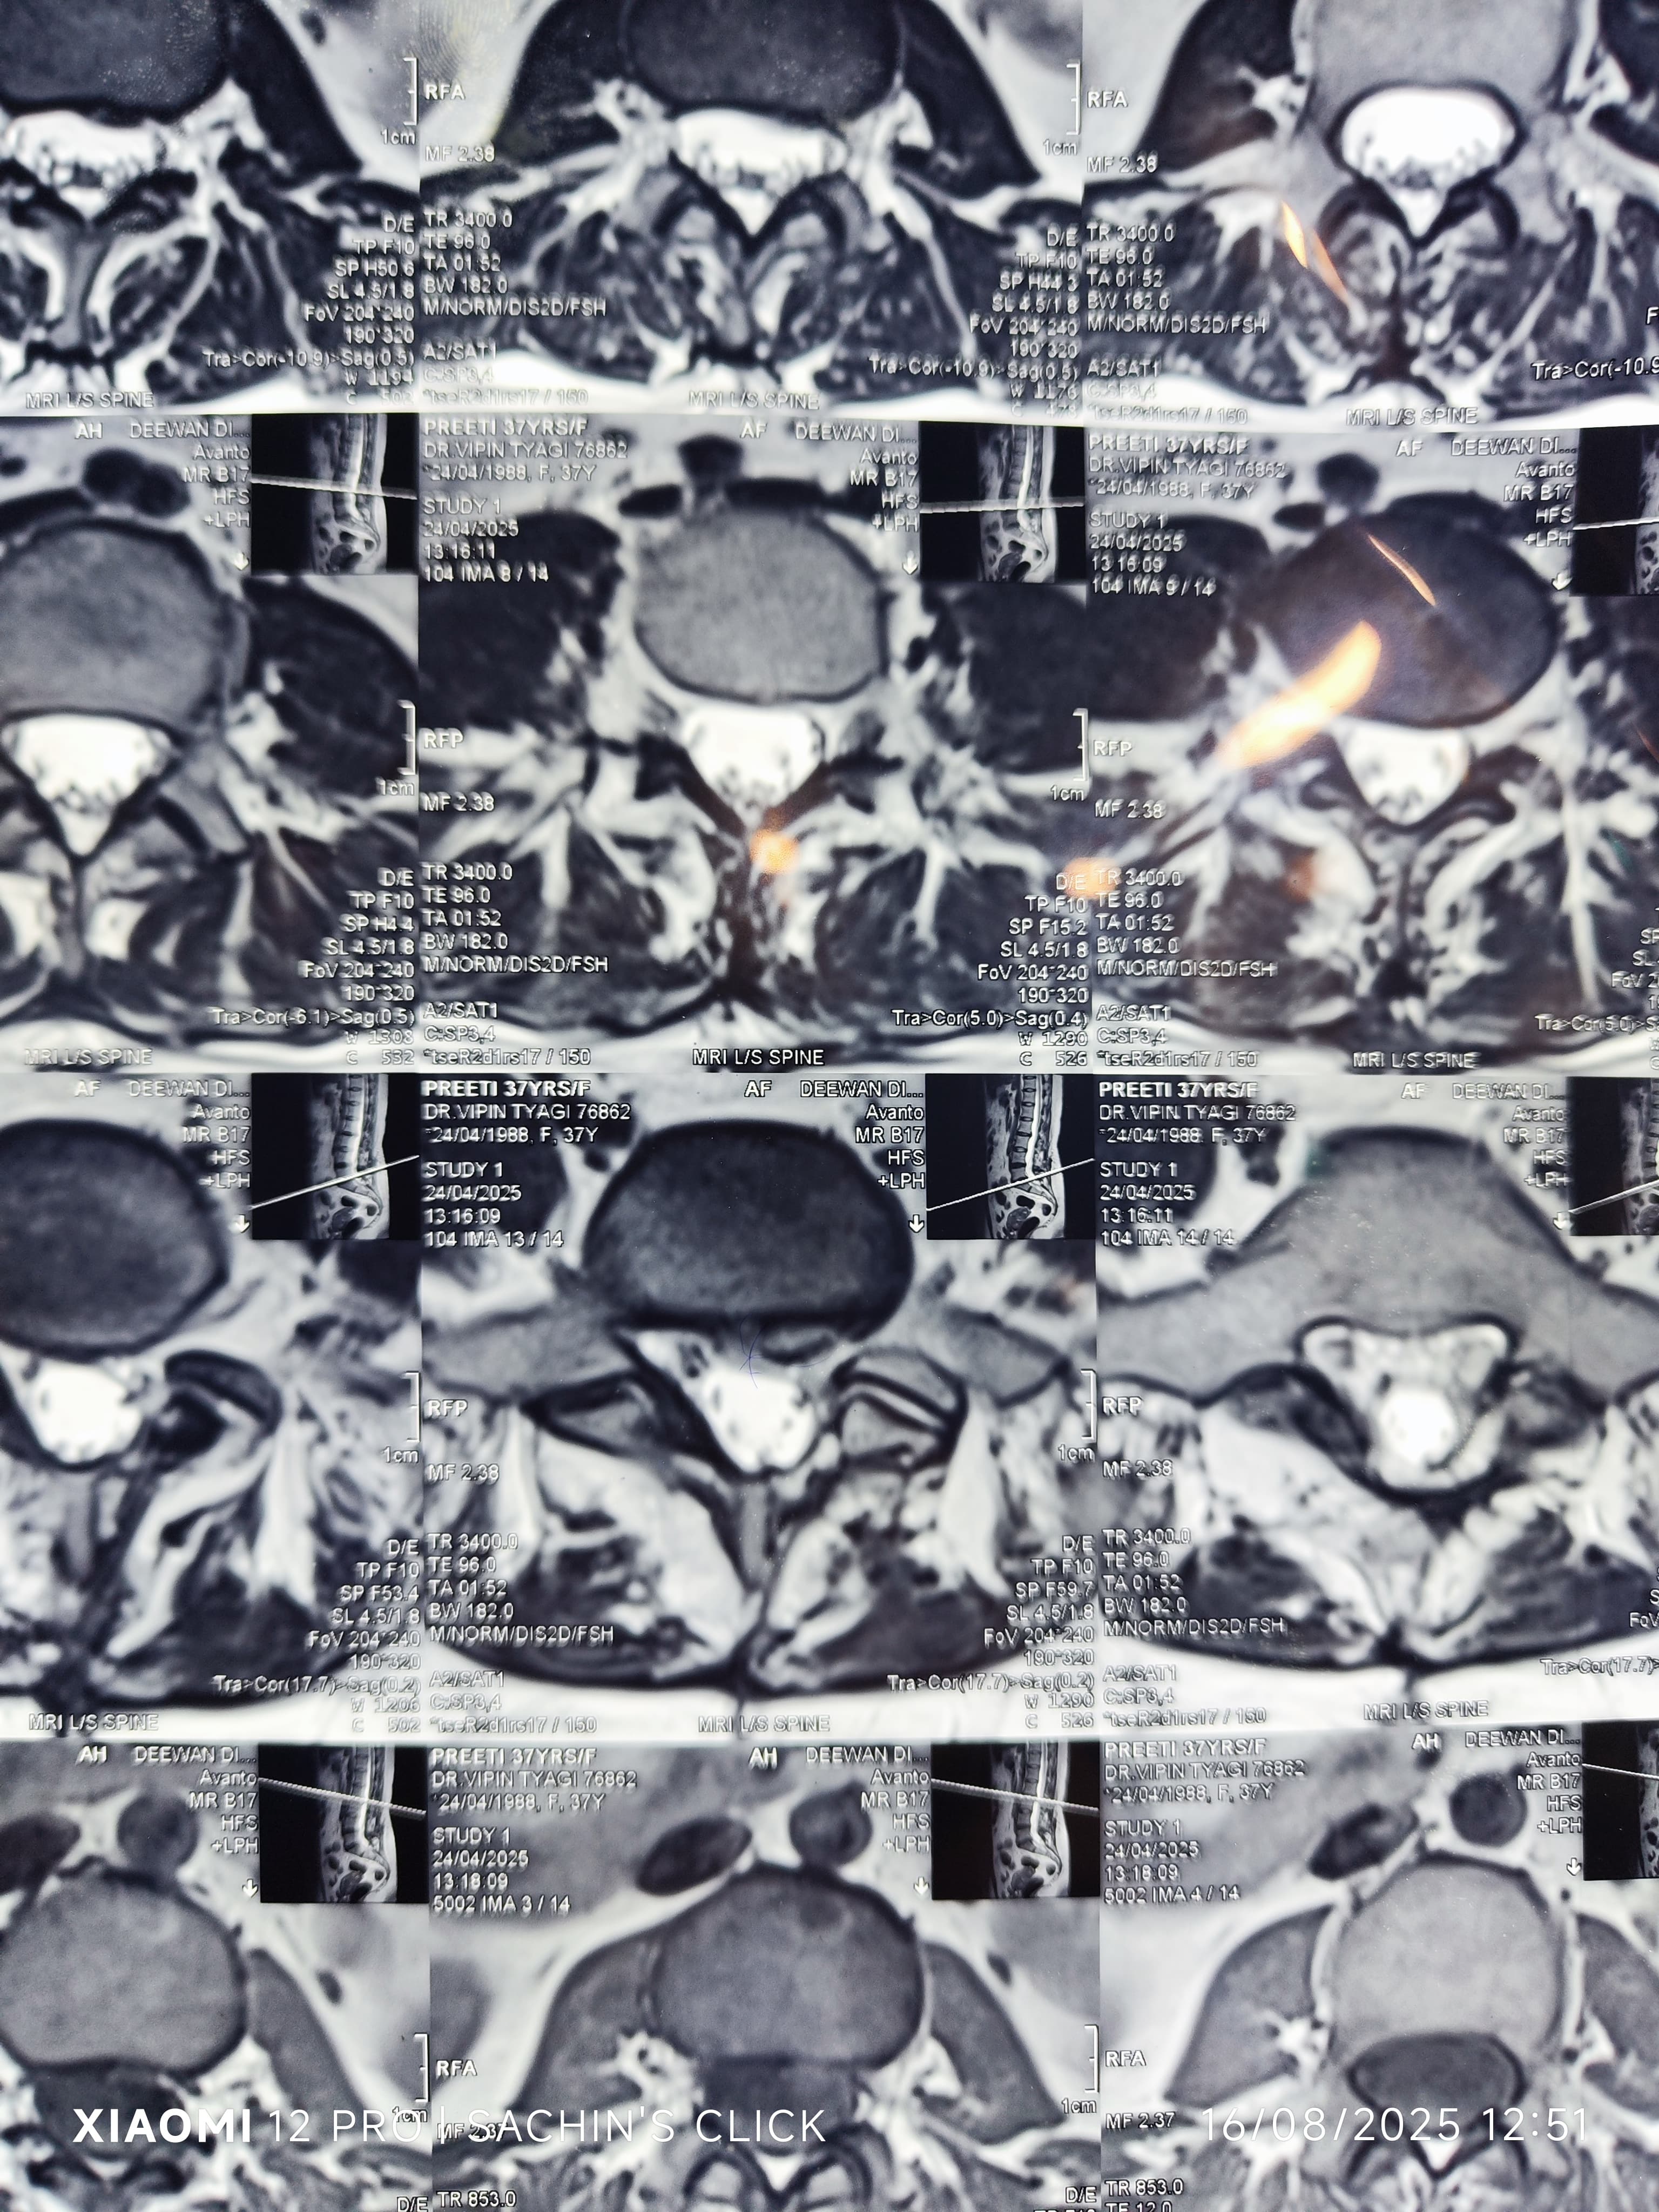

Glimpses of Advance Pain Care

Step inside our clinic and see our commitment to a healing environment and advanced care.